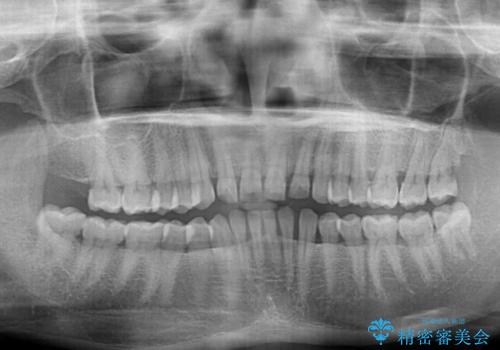

- 前歯の隙間と反対咬合を気にして来院された患者様です。

咬合力が強く、反対咬合の改善に時間がかかりましたが、その後はスムーズに進めることができました。